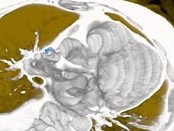

影像检查如图,最可能的诊断是()

• A.正常结构

• B.心房血栓

• C.心脏息肉

• D.心房黏液瘤

• E.以上都不是